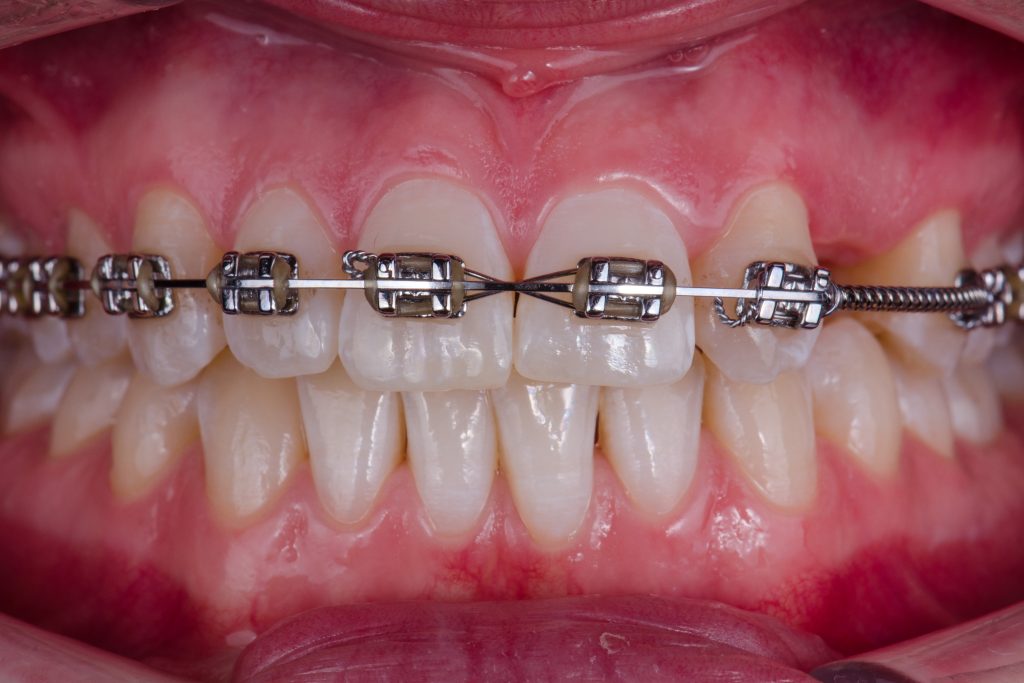

A 24-year-old female patient referred by an orthodontist who resolved the unilateral agenesis of the left upper lateral incisor by mesializing the left upper cuspid and shifting the gap in between teeth 23 and 25. After confirming the free bone corridor between the roots of the cuspid and the first bicuspid, a Straumann BLX RB implant (3.75 mm) was inserted and thin soft tissue buccally augmented with tuberosity connective graft. A sliding island flap on the palatal side relieved tension while suturing both sides of the mucosa. Three months later, the ortho appliance was removed and a temporary crown (Cerasmart) was delivered. All teeth were whitened and after four-month-period, an all-ceramic crown (Katana) was made and fixed. The patient denied and reshaping of the tooth 23. In 3 years, the situation is sthbilized however the prognosis of the tissue covering the tooth 23 is doubtful. Prosthetic part of the treatment done by a.krugova

surrounding teeth were bleached